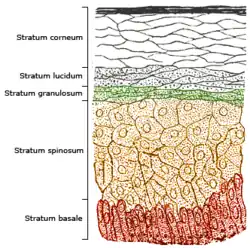

Cross-section of all skin layers Illustration of epidermal layers

Illustration of epidermal layers Optical coherence tomography of fingertip